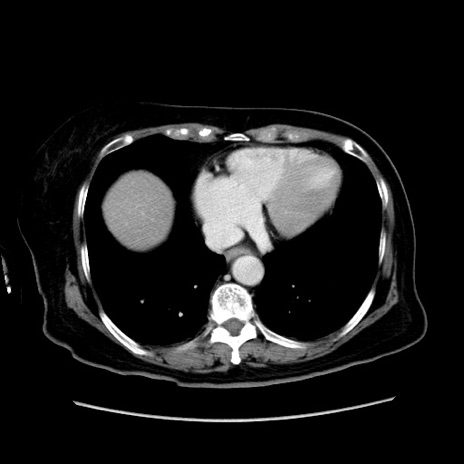

冠状断像

【症例】80歳代女性

【主訴】下腹部痛

【現病歴】約8時間前より下腹部痛の出現あり、救急外来受診。

【既往歴】両側付属器切除

【身体所見】意識清明、下腹部正中に手術痕あり、その部位に一致して圧痛と反跳痛あり。腸蠕動音は亢進。

【データ】WBC 9300、CRP 0.15